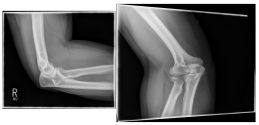

Ellenbogen2

Photo: A fracture with several framents

Ellenbogen3

Photo: The fracture on the left is after an operation with a plate and screws